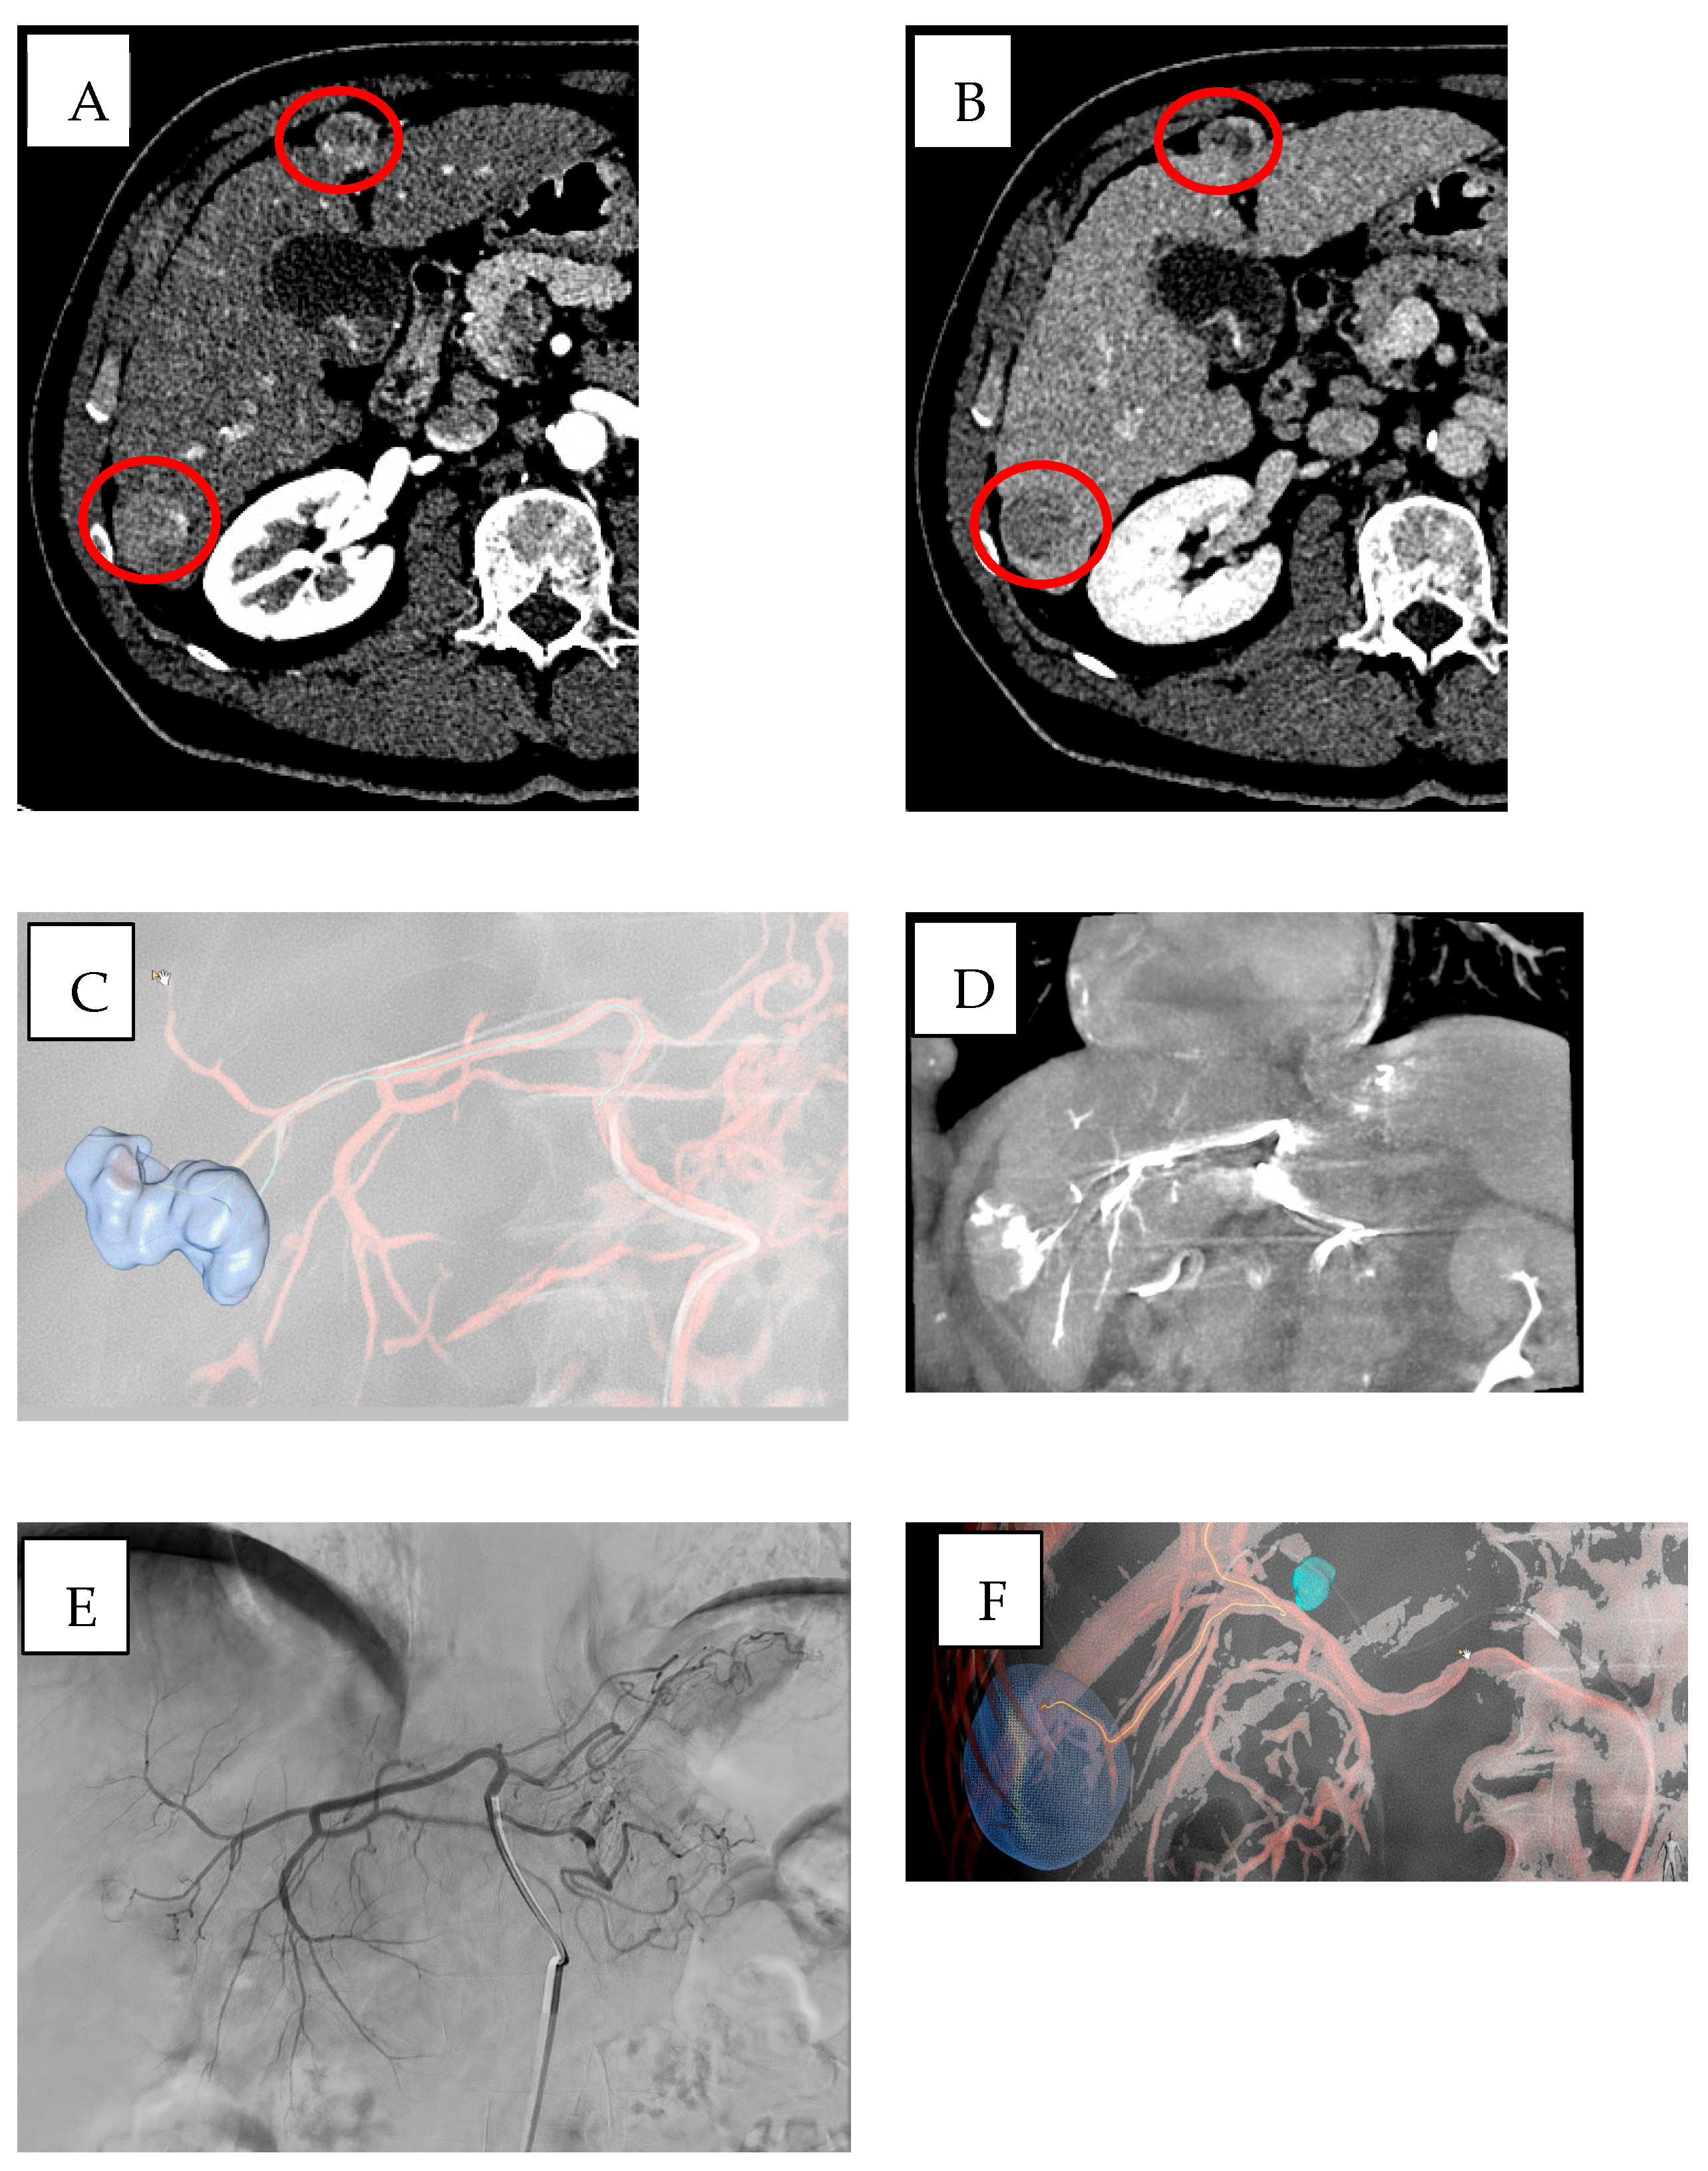

- Biondetti, P.; Ierardi, A.M.; Casiraghi, E.; Caruso, A.; Grillo, P.; Carriero, S.; Lanza, C.; Angileri, S.A.; Sangiovanni, A.; Iavarone, M.; et al. Clinical Impact of a Protocol Involving Cone-Beam CT (CBCT), Fusion Imaging and Ablation Volume Prediction in Percutaneous Image-Guided Microwave Ablation in Patients with Hepatocellular Carcinoma Unsuitable for Standard Ultrasound (US) Guidance. J. Clin. Med. 2023, 12, 7598. [Google Scholar] [CrossRef]

- Abi-Jaoudeh, N.; Kruecker, J.; Kadoury, S.; Kobeiter, H.; Venkatesan, A.M.; Levy, E.; Wood, B.J. Multimodality image fusion-guided procedures: Technique, accuracy, and applications. Cardiovasc. Intervent. Radiol. 2012, 35, 986–998. [Google Scholar] [CrossRef]